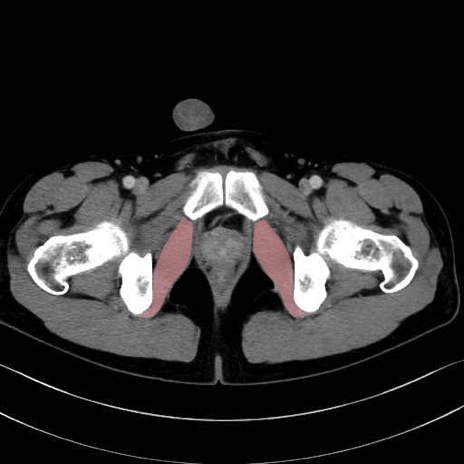

内閉鎖筋 (Obturator internus)